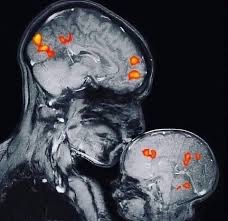

Mutter und Kind im fMRT (Quelle: Rebecca Saxe, MIT)